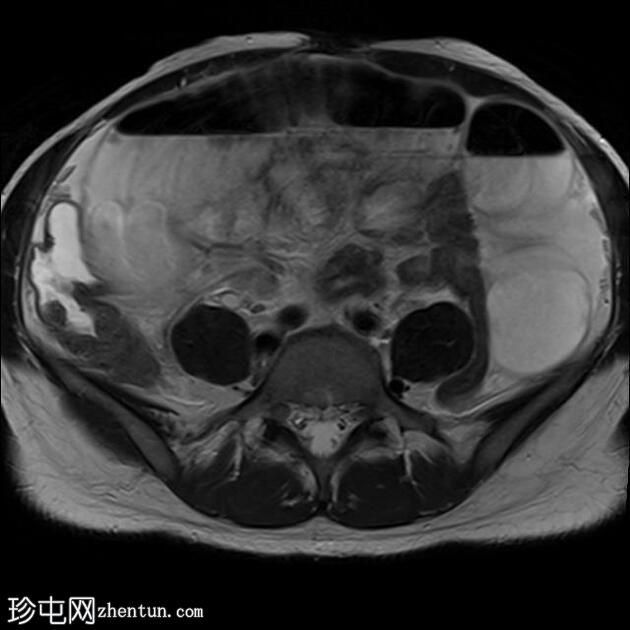

轴位增强CT

CT

CT显示盆腔内复杂肿块,包含囊性及更复杂的高密度成分。

盆腔内可见分层复杂液体